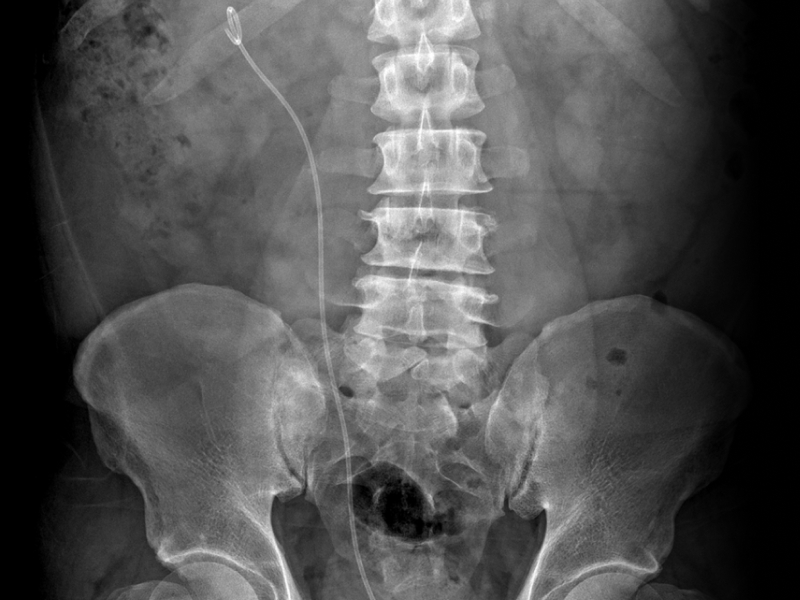

It’s Advanced! 요관내시경 결석 제거술,

골드만이 앞서가는 이유 BIG 5

보통 1~2일 내 퇴원하며 가벼운 활동은 빠르게 가능합니다. 스텐트는 며칠 후 제거합니다.

요관 손상, 출혈, 감염, 잔석 등의 부작용이 드물게 발생할 수 있으나 대부분 경미하고 일시적이며 적절한 조치로 회복이 잘 됩니다.

수술 후 하루 이내 가벼운 활동은 대부분 가능합니다. 무거운 물건 들기나 격한 운동은 1~2주간 피하는 것이 좋습니다. 스텐트가 있다면 제거 후 더욱 편하게 생활할 수 있습니다.

하루 2리터 이상 물을 마셔 소변량을 충분히 유지하는 것이 중요합니다. 식단 조절, 결석 성분 분석, 정기 검진도 큰 도움이 됩니다. 재발률이 높은 질환이므로 꾸준한 관리가 필요합니다.

수술 후 요관 부종이나 폐쇄를 방지하기 위해 대부분 삽입합니다. 이는 불편감은 있을 수 있지만 요관 회복에 중요한 역할을 하며 보통 1~2주 후 외래에서 간단히 제거합니다.